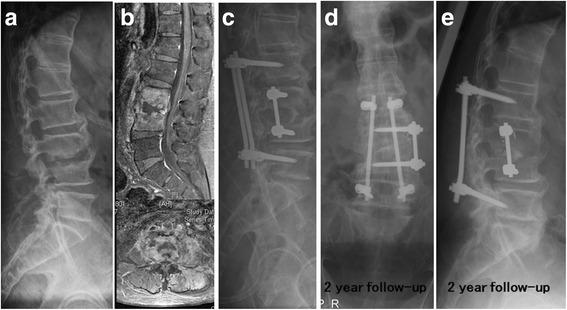

From January 2003 to January 2013, 54 patients who underwent combined antibiotic and surgical therapy in the treatment of hematogenous pyogenic spondylodiscitis were included.

Compared with 37 GPC-HPS patients, the 17 GNB-HPS patients were more often found to be older individuals, a history of cancer, and a previous history of symptomatic urinary tract infection. They also had a less incidence of epidural abscess formation compared with GPC-HPS patients from findings on magnetic resonance imaging (MRI). Constitutional symptoms were the primary reasons for initial physician visits in GNB-HPS patients whereas pain in the affected spinal region was the most common manifestation in GPC-HPS patients at initial visit. The clinical outcomes of GNB-HPS patients under combined surgical and antibiotic treatment were not different from those of GPC-HPS patients. In multivariate analysis, independent predicting risk factors for GNB-HPS included a malignant history and constitutional symptoms and that for GPC-HPS was epidural abscess.

与37例GPC-HPS患者相比,17例GNB-HPS患者年龄更大、更多有癌症病史及既往有症状性尿路感染史。磁共振成像(MRI)结果显示,与GPC-HPS患者相比,他们硬膜外脓肿形成的发生率更低。全身症状是GNB-HPS患者初次就诊的主要原因,而受累脊柱区域疼痛是GPC-HPS患者初次就诊时最常见的表现。联合手术及抗生素治疗的GNB-HPS患者的临床结局与GPC-HPS患者无异。多因素分析中,GNB-HPS的独立预测危险因素包括恶性病史和全身症状,GPC-HPS的独立预测危险因素是硬膜外脓肿。